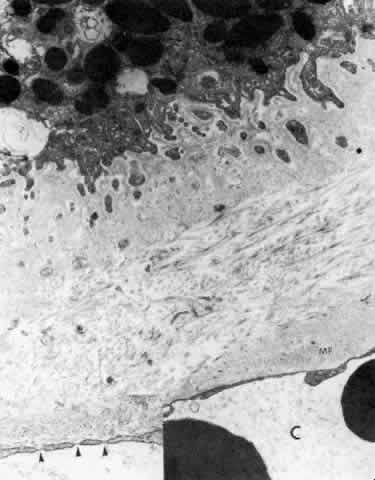

There are a large number of intercellular junctions between the ciliary epithelial cells, each giving important data about the specific functions of these cells (see Fig. 11). Toward the base of the NPE cells their lateral sides are joined by desmosomes (see Fig. 15). At their apical ends they are connected by typical tight junctional complexes consisting of a zonula occludens and zonula adherens (Fig. 19). These tight junctions represent the primary blood-aqueous barrier in the ciliary body. When large tracer molecules such as horseradish peroxidase are injected intravenously into primates,20,21 the tracer has an easy passage through the fenestrated capillaries of the ciliary processes, but does not pass beyond the apices of the NPE cells (see Fig. 19).

Fig. 19. Evidence of tight junctional complexes in the anterior ciliary epithelium of Macaca mulatta. The pigmented epithelial cells (PC) are outlined by a thin black line that is the reaction product of horeseradish peroxidase, a tracer substance injected intravenously in vivo. The tracer has entered the intercellular spaces of the nonpigmented epithelium (NPC) but is held up by occluding junctions (arrowheads), preventing further progress into the posterior chamber. (X 8450; Courtesy of Dr. Guiseppina Raviola)